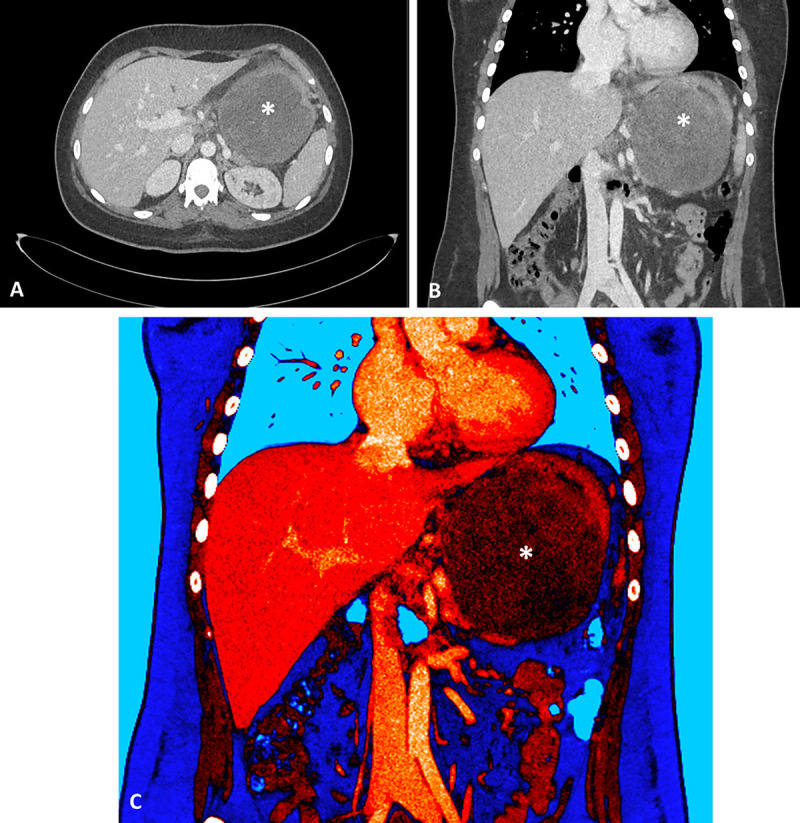

Succinate dehydrogenase-deficient gastrointestinal stromal tumor of the stomach: EUS and contrast-enhanced EUS features (with videos).